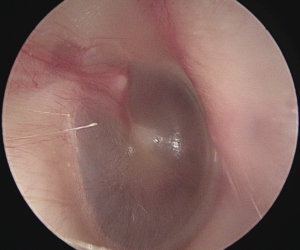

Look at the picture of what you see through the otoscope when looking inside Ben’s left ear.

2. Does the inside of Ben’s left ear look healthy?

No is correct!

Ben’s left ear does not look healthy. The eardrum is red and bulging.

It is important to also check Ben’s right ear.